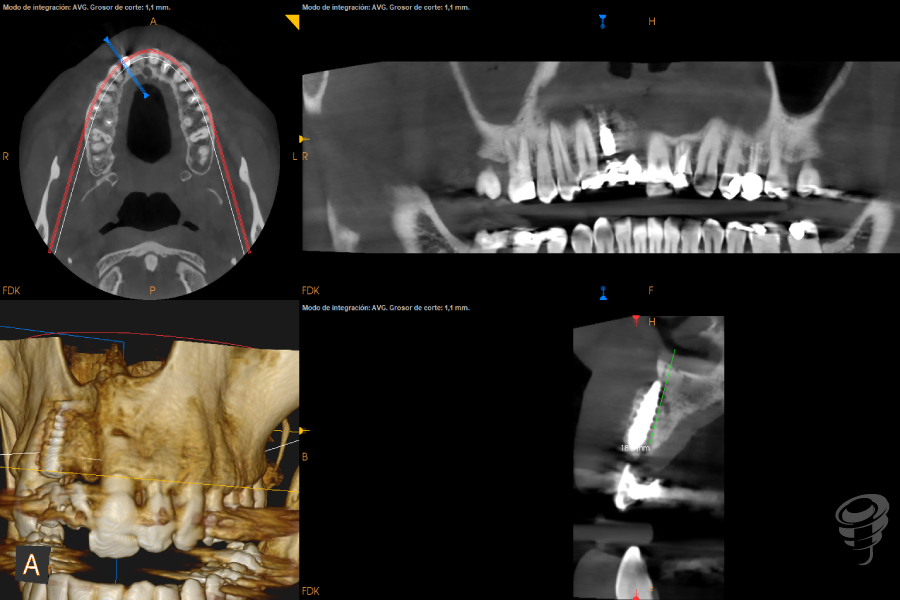

Realizamos un estudio con un CBCT de la zona. En los cortes seccionales se visualiza el implante en una posición muy vestibular, fuera del marco óseo y una imagen radiolúcida rodeando el implante.

Imagen 3